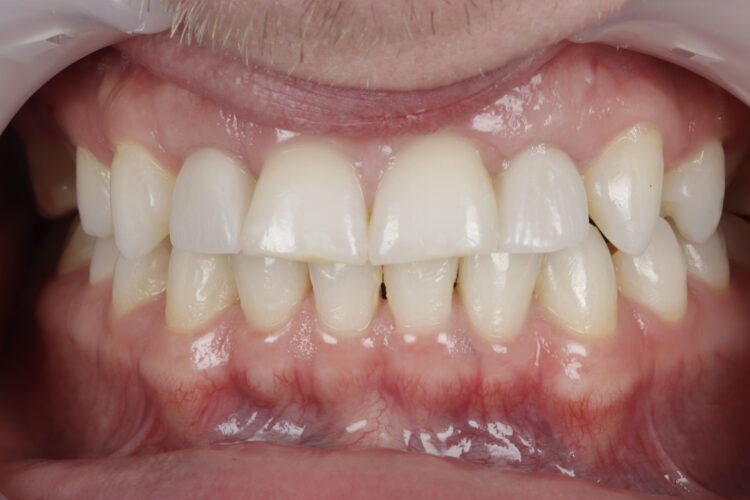

Final crowns placement (November 2023)

The final implant crowns were fitted in November 2023. There was a slight delay due to the patient postponing some appointments and undergoing whitening treatment.

Outcome

The patient achieved an aesthetically pleasing and functional result and he expressed satisfaction with the outcome.